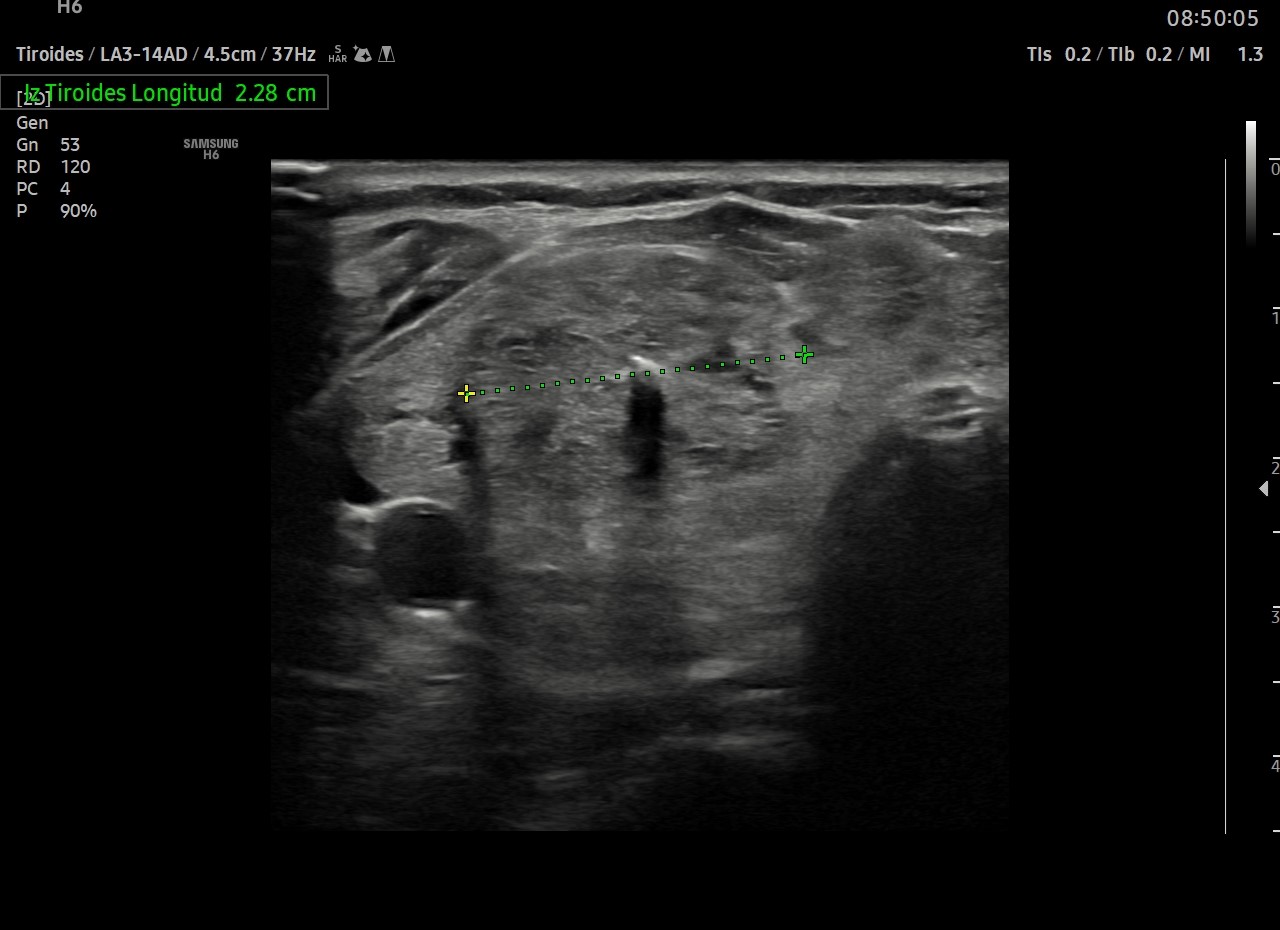

Ecografía tiroidea

Tiroides prácticamente ocupado en su totalidad por múltiples nódulos, el mayor en LTD, de aproximadamente 2,8 cm con una calcificación en su zona central (Tirads 4) (ya realizada PAAF previa)

El resto de tiroides muestra una ecogencidad desestructurada. Vascularización normal.

ID. Bocio multinodular.

Nódulo tirads 4 (PAAF previa)

Afectación marcada de la ecogenicidad probablemente por tiroiditis.